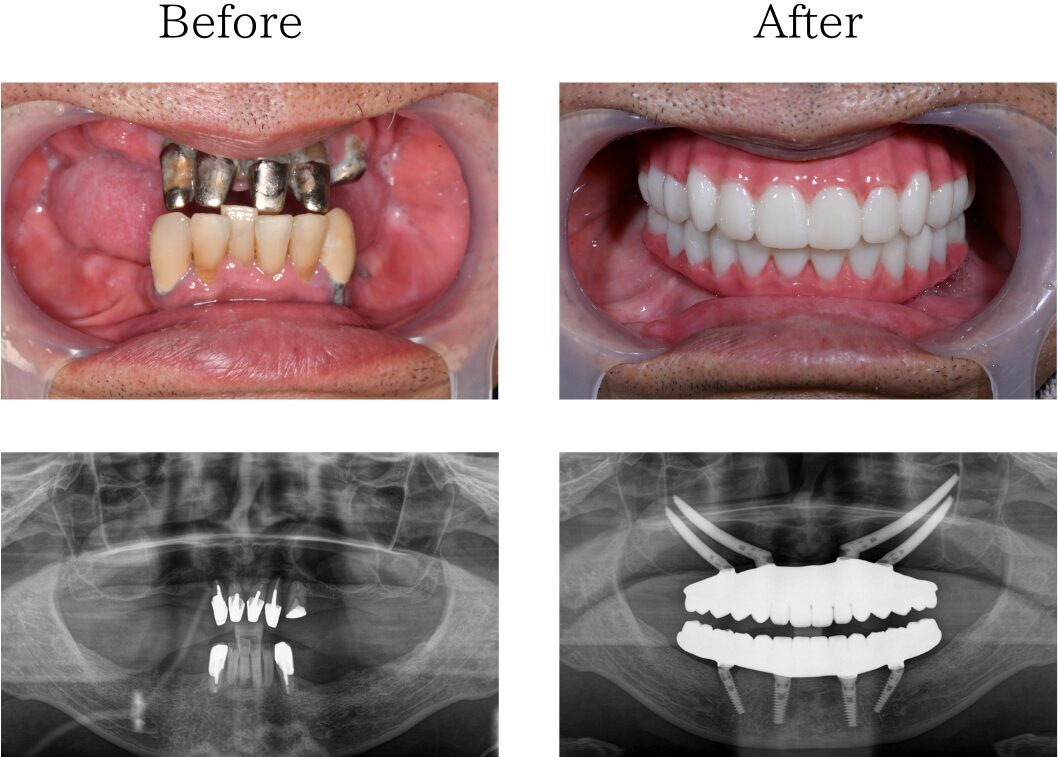

難症例 インプラント

※治療内容:上下顎オールオン4

※費用:3,760,000円*モニター価格

※期間:半年

※リスク:出血、痛み、腫れ、しびれ

「苦手な人付き合いを克服したい」

40代 女性 (大分) の場合

私は人付き合いが苦手で、歯医者に行くにしても何か思われたらどうしようと思い、治療に通えませんでした。そのせいで虫歯をそのままにして歯が溶けたり、歯が抜けてもそのままにしていたらボロボロになり、差し歯をしてもすぐ外れたりしてどの治療が合うのか分かりませんでした。ネットで調べていたところオールオン4という治療があることを知り、遠方ですがHPに記載されていた大多和先生の言葉を信じ福岡での治療を決めました。